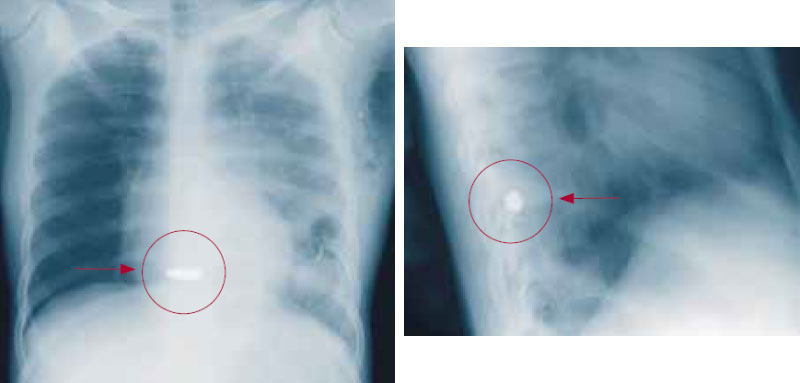

Если инородное тело находится неглубоко, особенно над точкой опоры (в ладонной поверхности кисти, в подошве ступни, в области локтевого сустава и т. д.), оно может причинять сильную боль (рисунок 10). Извлечение можно производить в плановом порядке после заживления острой травмы.

Рисунок 10. Металлический осколок находится в точке опоры – в подошве ступни